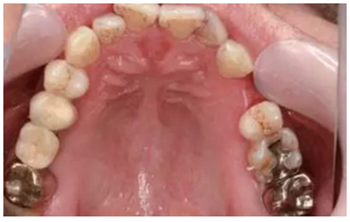

從圖1可以看出患者缺牙區(qū)的間隙充足,牙齦健康,頰側(cè)軟組織略有凹陷。

圖1 缺牙區(qū)的頰側(cè)和口內(nèi)照片